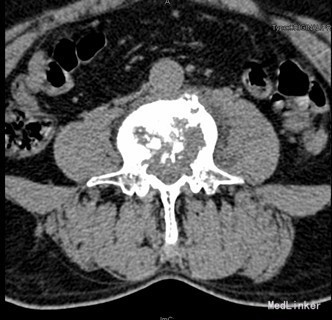

查体:腰4、5棘突轻度叩压痛,双侧大腿后外侧小腿外侧及足背感觉功能减退,以右侧明显。 辅查:CT示腰4椎体骨质破坏并增生、硬化改变,以骨质破坏为主,左侧椎旁软组织肿块形成,结核?肿瘤待排。腰4、5腰5骶1椎间盘突出。腰椎退行性变。MRI示腰4椎体骨质破坏,性质?腰4、5腰5骶1椎间盘突出,腰椎退行性变,双侧髂骨信号不均匀,性质?

初步诊断:腰4椎体骨质破坏:结核?肿瘤? 诊疗计划:经前路腰4椎体部分切除,椎管减压,取自体髂骨植骨融合,Antares内固定术

术中见腰4椎体骨质破坏,其内可见空腔形成,周围骨质硬化,左侧椎旁椎体空腔内可见少量干酪样坏死组织,腰3、4椎间盘破坏、碎裂,部分组织突入椎管,压迫硬膜囊,取坏死组织术中冰冻切片示:肉芽肿性炎症伴坏死。